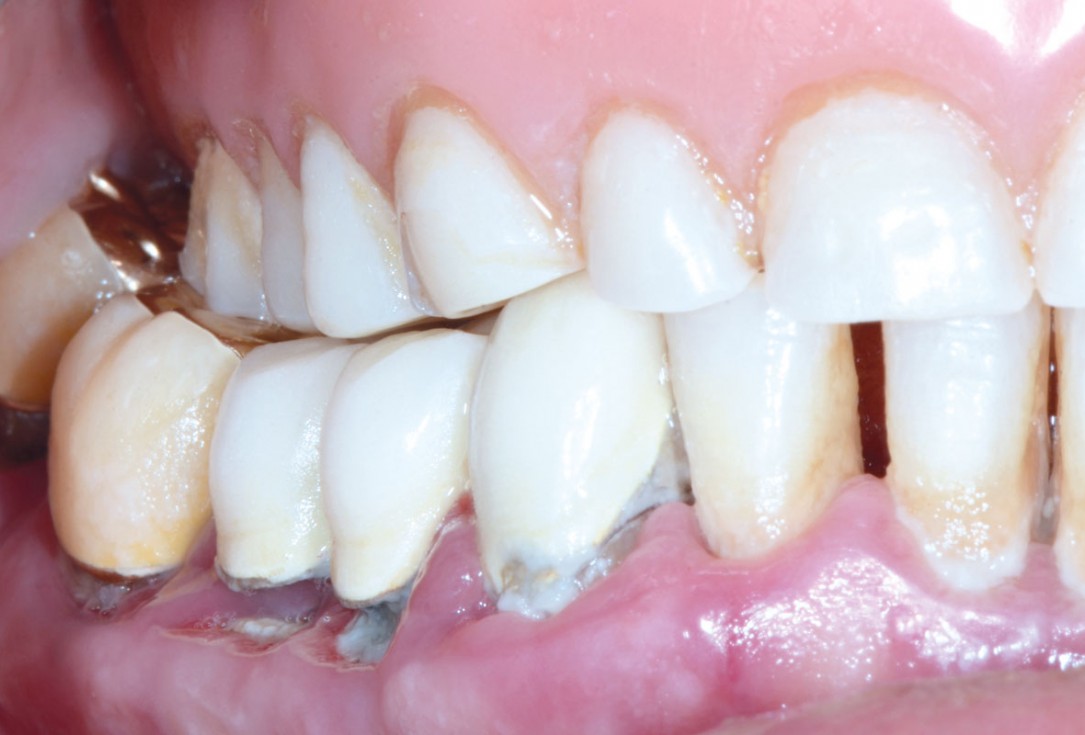

Multiple socket preservation in the mandibular with collacone® max – Dr. D. Jelušić